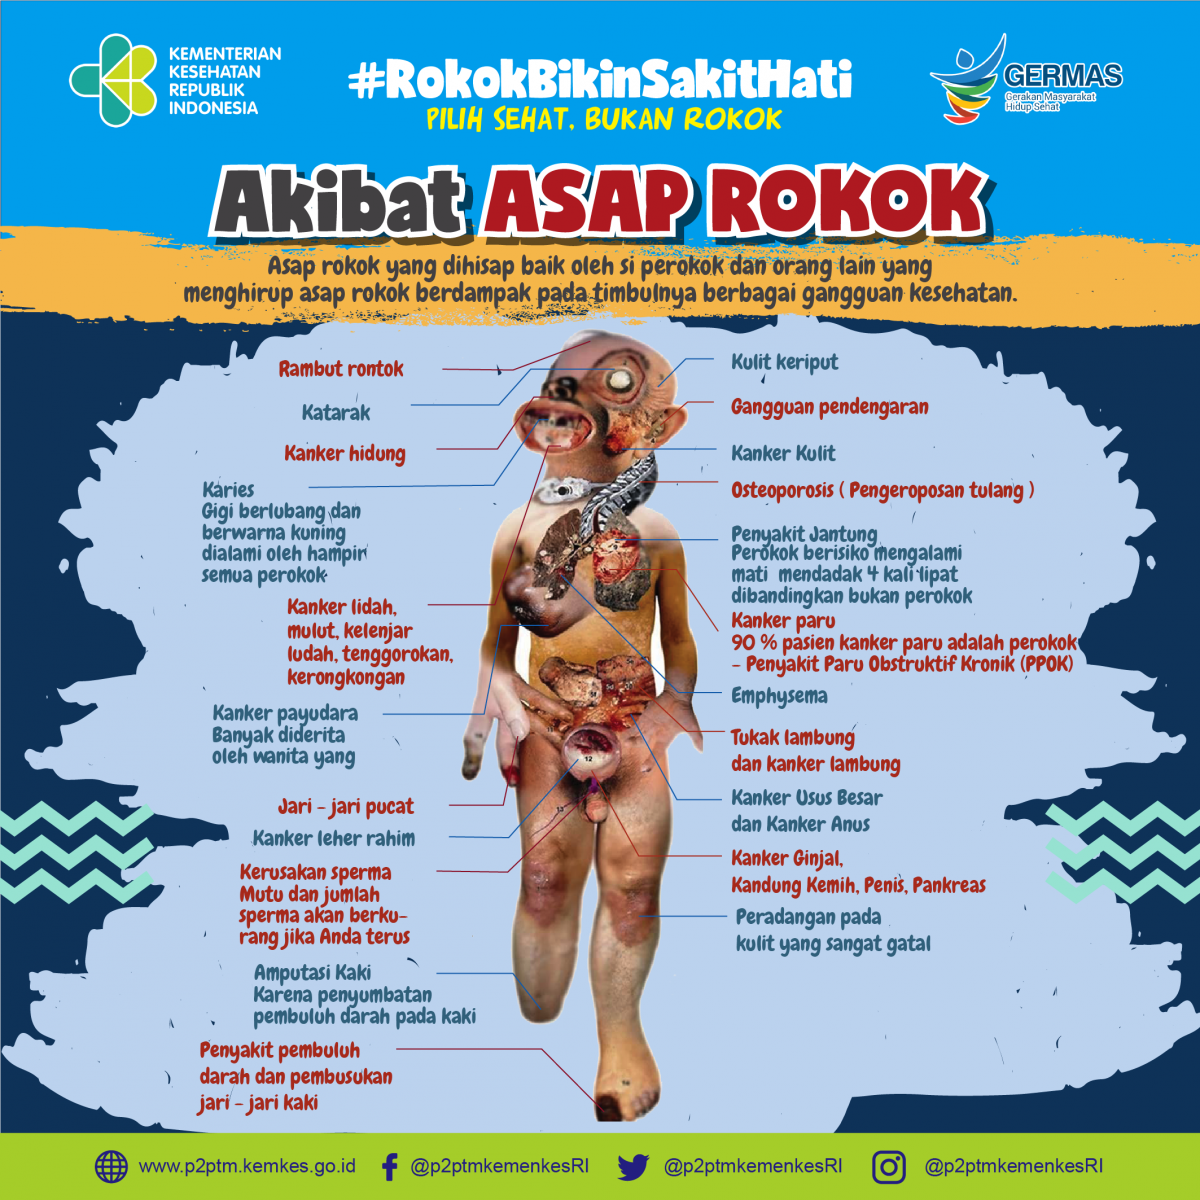

Akibat Asap Rokok Direktorat P2ptm

Akibat Asap Rokok Direktorat P2ptm

Gambaran Akibat Asap Rokok Direktorat P2ptm

Gambaran Akibat Asap Rokok Direktorat P2ptm

Akibat Asap Rokok Direktorat P2ptm

Akibat Asap Rokok Direktorat P2ptm

Apa Saja Akibat Asap Rokok Direktorat P2ptm

Apa Saja Akibat Asap Rokok Direktorat P2ptm